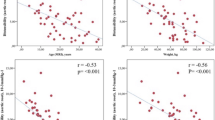

Characteristics of the CoA patients and subgroups are shown in Table 1. Non-significant correlations within the entire patient population (n = 21) were found between the following parameters: the age at correction and MRI, PWV in the proximal and descending aorta, PWV ratio, and peak WSS in the ascending aorta, aortic arch, and descending aorta. And, for the same parameters, non-significant group differences between the BAV and TAV subgroups were found (respectively, n = 12 and n = 9). For patients with a TAV, a significant good correlation was found between age at correction and descending aorta PWV (rs = 0.80, p = 0.010, Fig. 2), indicating higher values of descending aorta PWV for patients with a TAV that underwent correction of CoA at an older age. Such a correlation was absent for patients with BAV. Between the subgroups without reobstruction and with reobstruction (respectively, n = 12 and n = 9), significant differences were found for the peak WSS in the aortic arch (3.9 ± 1.3 Pa versus 6.5 ± 2.2 Pa, respectively; p = 0.003) and descending aorta (5.0 ± 1.3 Pa versus 6.7 ± 1.1 Pa, respectively; p = 0.005), indicating higher peak WSS values for patients with a reobstruction proximally and distally to the lesion. The statistical analysis within subgroups subdivided on both the aortic valve morphology and the presence of reobstruction was not performed, due to small population sizes within these subgroups. Examples of three-dimensional magnitude WSS maps of patients, subdivided on the aortic valve morphology and the presence of reobstruction, are shown in Fig. 3. The examples demonstrate higher peak WSS in the aortic arch and descending aorta for patients with reobstruction compared to those without reobstruction.

The observed positive correlation for TAV subgroup between the age at correction and descending aorta PWV suggests that a prolonged period of abnormal haemodynamic exposure may result in increased aortic wall stiffening. Specifically for TAV patients, this is in line with the hypothesis that for CoA patients, a curative reconstruction at a younger age will result in less wall stiffening, thus a lower PWV. This result should be interpreted with caution, since no correlation was found within the entire patient group nor in the BAV subgroup. The absence of a comparable correlation for these groups may be explained by the abnormal haemodynamics of BAV patients [25], potentially resulting in different disease progressions for both aortic valve morphologies. Therefore, the significant finding in the TAV subgroup (notably, smaller in size than BAV subgroup) represents an evaluation of the CoA correction for patients selected on valve morphology. The abnormal haemodynamics of BAV patients results in more diversity of flow patterns within the entire patient population and subsequently may decrease the probability of detecting a significant effect. However, Voges et al. [19] observed a weak but significant positive correlation (r = 0.33) between the age at correction and the descending aorta PWV within their entire patient group, incorporating 16 BAV and 35 TAV patients. This effect presumably may be influenced by substantial larger group of TAV patients compared to BAV patients. Unfortunately, these authors did not statistically analyse this correlation separately within both aortic valve morphology subgroups.